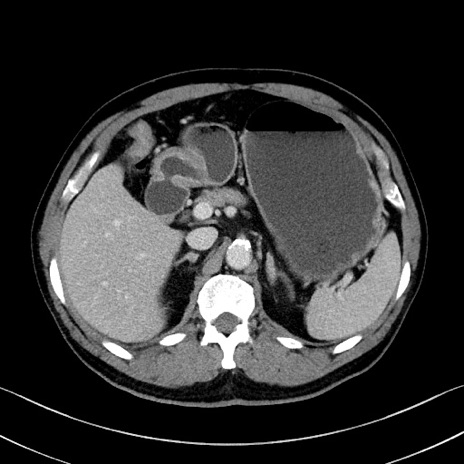

症例35(横断像)

冠状断像

【症例】70歳代 男性

【主訴】腹部膨満、嘔吐

【現病歴】昨日より腹部膨満感出現。本日増悪し、仙痛出現。嘔吐あり、受診。

【既往歴】糖尿病、胆摘後

【身体所見】BP 149/80mmHg、HR 74/min、BT 35.9℃、腹部:膨満、軟、圧痛なし。腸雑音減弱あり。上腹部正中切開瘢痕あり。

【データ】WBC 13500、CRP 1.72